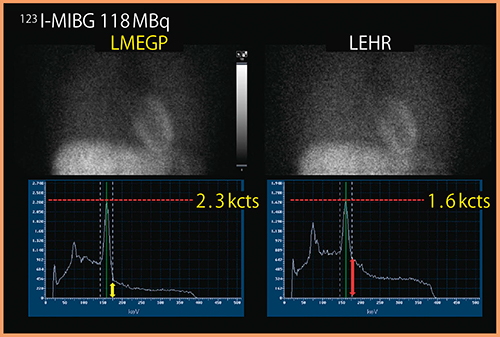

コリメータにも大きな特長がある。標準装備である低中エネルギー汎用パラレルホールコリメータ(LMEGP)は,感度,位置分解能,ペネトレーションのバランスを取り,心筋SPECT検査に最適化している。

低エネルギー高分解能パラレルホールコリメータ(LEHR)と比較して約1.8倍の感度があるため,心電同期収集や99mTc製剤に比して投与量の少ない201Tl製剤でも,統計ノイズが少ない高画質な画像が得られる。

また,123I核種に見られる529keV由来の散乱線成分の混入を抑え,心縦隔比(H/M比)の定量性を改善する(図3)。

図3 LMEGPコリメータとLEHRコリメータの比較

(データご提供:国立循環器病研究センター様)